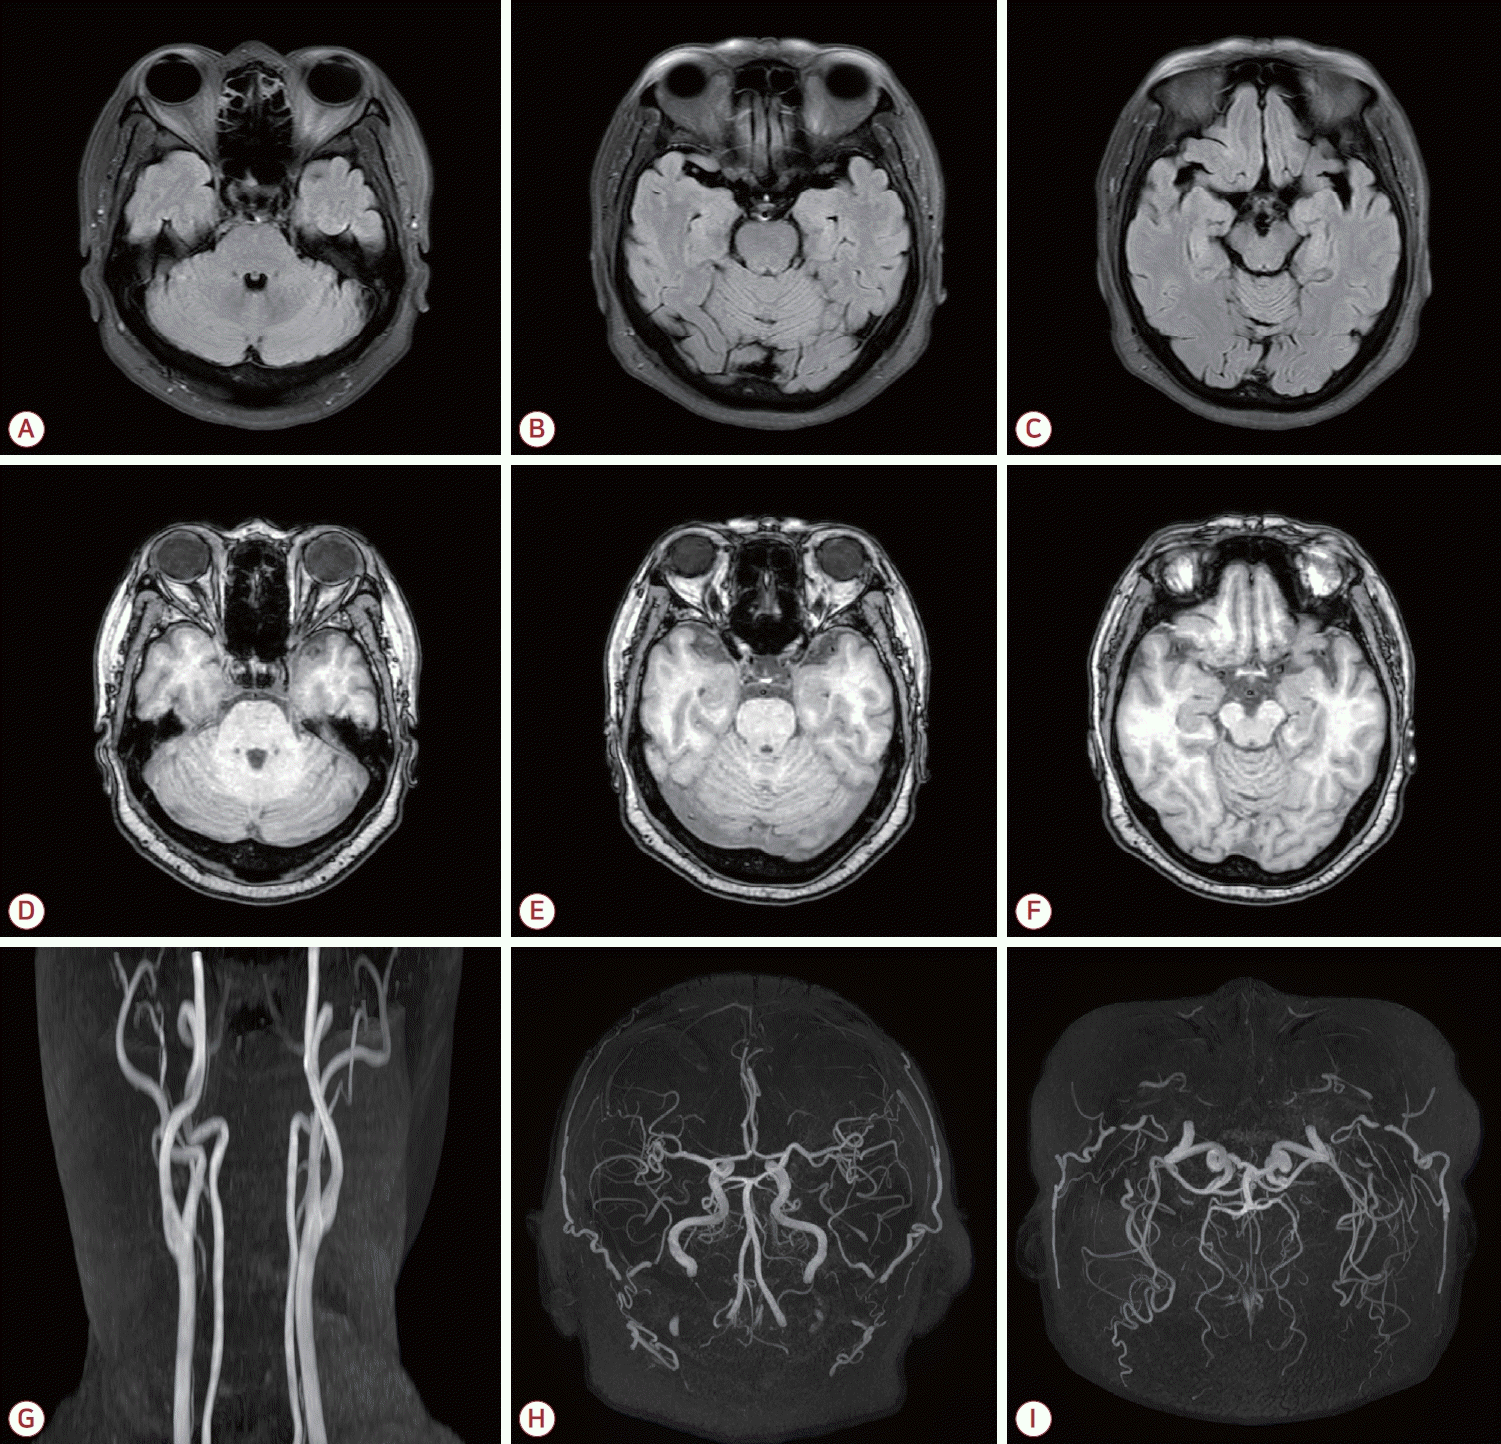

환자는 6년 학력이었으며 2024년 8월에 시행된 서울신경 심리선별종합검사(Seoul Neuropsychological Screening Battery, SNSB) 결과 기억력, 전두엽기능 그리고 시공간 인지기능의 저하 소견을 보이는 다영역, 기억상실형 경도인지장애(amnestic mild cognitive impairment [MCI], multiple domain) 상태였다. 간이정신상태 검사(mini-mental state examination, MMSE) 점수는 25점, 임상치매평가척도(clinical dementia rating, CDR)는 0.5단계, CDR-sum of box (SB)는 2.5점이었다. SNSB-dementia version (SNSB-D)의 종합 점수(composite score)는 106점이었다. 2024년 8월 시행된 뇌MRI에서 좌측 해마(hippocampus)와 해마곁이랑(parahippocampal gyrus), 좌측 후두엽(occipital lobe), 양측 소뇌(cerebellum)에서 만성 뇌경색 소견을 보였으며 뇌MRA는 정상이었다(Fig. 2-A-F). 심전도와 24시간 홀터 검사 소견은 정상이었다. 환자에게 아스피린과 뇌활성화제를 처방하였으며 뇌 병변의 변화를 확인하기 위하여 2025년 5월 뇌MRI를 재시행하였고 특별한 변화는 없었다(Fig. 2-G-I). 2025년 5월에 시행된 SNSB 검사상 기억력, 집중력 그리고 시공간 인지기능의 저하 소견을 보이는 amnestic MCI, multiple domain 상태였으며 MMSE 점수는 25점, CDR은 0.5단계, CDR-SB는 2.5점이었다. SNSB-D의 종합 점수는 138점으로 전반적인 인지기능의 호전 소견을 보였다(Fig. 3).

Figure 2.

MRI at the time of diagnosis of vascular cognitive impairment secondary to MPO-ANCA-associated vasculitis demonstrates hyper-intensities in both cerebellar hemispheres (A) and the left parahippocampal and occipital gyri (B-C) on FLAIR images, with corresponding hypo-intensities in the same regions on T1-weighted images (D-F). Follow-up FLAIR images obtained 8 months later (G-I) show no interval change. MRI; magnetic resonance imaging, MPO; myeloperoxidase, ANCA; antineutrophil cytoplasmic antibody, FLAIR; fluid attenuated inversion recovery.